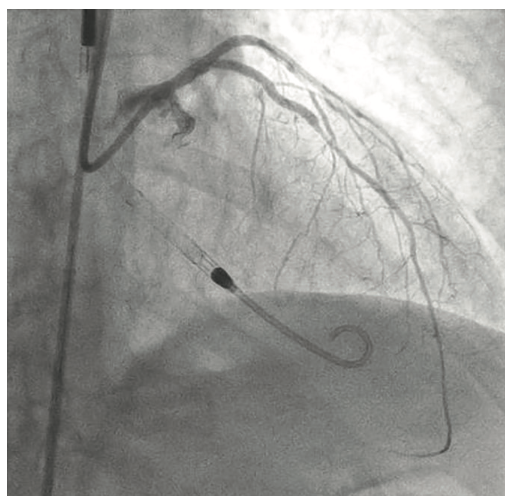

A 54-year-old female with a history of peripheral arterial disease (PAD), tobacco abuse, diabetes, severe chronic obstructive pulmonary disease (COPD), obesity, hypertension, and hyperlipidemia presented to an outside hospital with a non-ST-elevation myocardial infarction (NSTEMI). Subsequent left heart catheterization revealed a chronic total occlusion (CTO) of the left anterior descending coronary artery (LAD) and left circumflex (LCx), with a 95% ostial ramus and a patent right coronary artery (RCA) with right to left collaterals (Figures 1-2). Initial ejection fraction by ventriculogram was approximately 30-35%. She was turned down for surgery and subsequent studies revealed viable myocardium; therefore, she was scheduled for percutaneous revascularization with mechanical circulatory support using an Impella left ventricular assist device (Abiomed). She was found to have bilateral occlusion of her iliac stent (Figure 3). It was decided to revascularize at least one of her occluded iliac arteries, and then use the femoral and radial approach for dual access in order to recanalize the CTO. The axillary artery would be used for the Impella, rather than advancing the 14 French (Fr) sheath through a freshly stented artery. The right iliac artery was revascularized and she was brought back to revascularize the left system.

The right groin was accessed using fluoroscopic guidance. A micropuncture sheath was placed and upsized to a 7 French, 45 cm Destination sheath (Terumo) in the right groin. We accessed the right radial, but could not get good flow. Therefore, we ended up using the ulnar artery with ultrasound guidance and placed a Terumo 5/6 Slender sheath in the ulnar artery. We proceeded to access the left axillary artery. We placed a Judkins right (JR)4 catheter in the left subclavian and did a selective angiogram, documenting the location of the thoracoacromial artery and circumflex humeral (Figure 4); then using a Chiba biopsy needle (Cook), accessed the axillary artery and placed a 5-French 30 cm sheath (Cook)(Figure 5). We used the 15 cm biopsy needle to allow us a shallow angle of approach with the patient’s body habitus and to avoid “kinking” the sheath. We then switched out for the Lunderquist wire (Cook Medical), placed an 8 Fr sheath, and performed a pre-close using two Perclose devices (Abbott Vascular) (Figure 6).